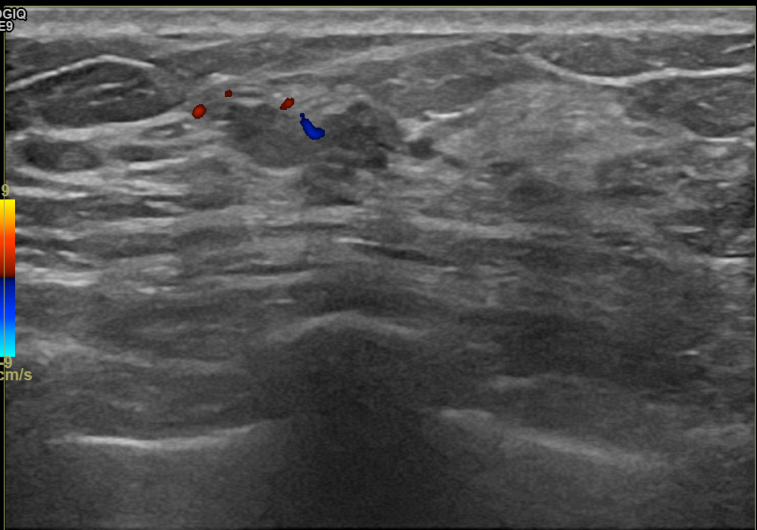

상기환자 외부검사이상으로  우측조직검사를위해  내원하신 40대중반 여성분으로

우측 조직검사 시행해 침윤성암으로 진단되었습니다